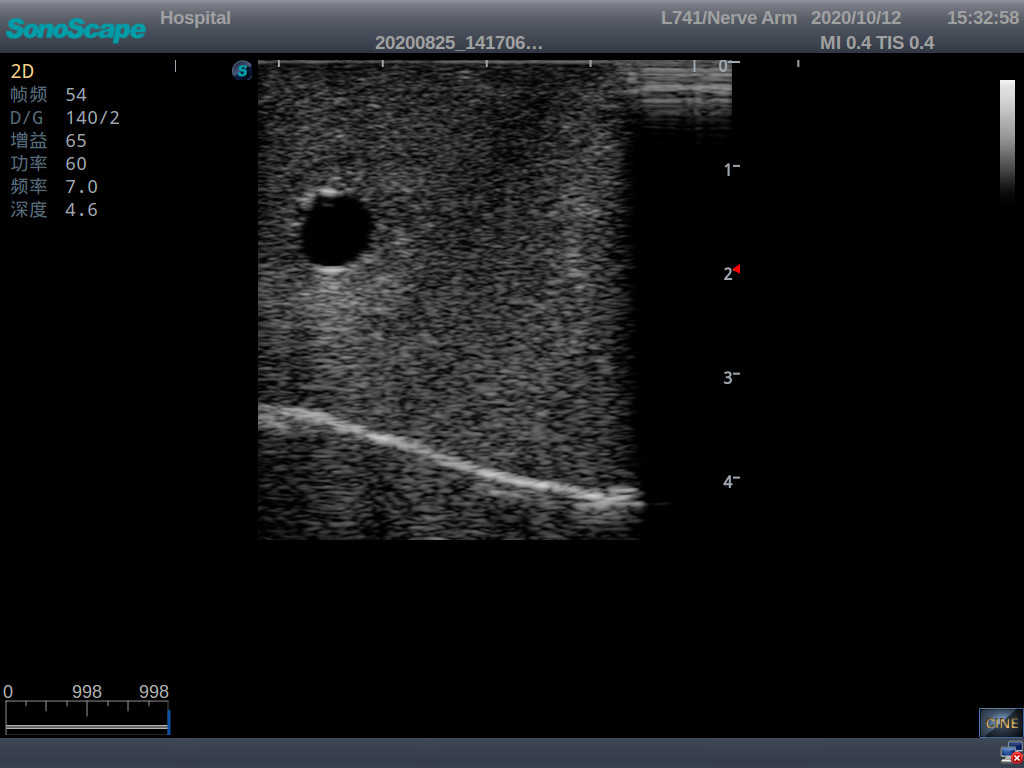

Central Venous Catheterization Ultrasound Training Model

Model TYE1510.2

It is a model from the earlobe plane to the umbilical plane with its head turned to one side. It's put in a standard central venipucture and catheterization position, including landmarks such as right arm, clavicle, ribs, sternocleidomastoid muscle, sternoclavicular joint, etc. It can be used for ultrasound-guided subclavian vein and internal jugular vein puncture and catheterization. The model's arm can be used for ultrasound-guided PICC catheter placement.

2)  The puncture module supports using a clinical real ultrasound machine to observe clear images such as right internal jugular vein, right common carotid artery, superior vena cava, right brachiocephalic vein, right brachiocephalic trunk, right subclavian vein, right subclavian artery, etc.

3)  The puncture pad at the arm is made of high-molecular ultrasound material, close to real skin. It can support the use of real ultrasound machines, and the images of tissue structures (skin, subcutaneous tissue, blood vessels) under ultrasound are clear and real